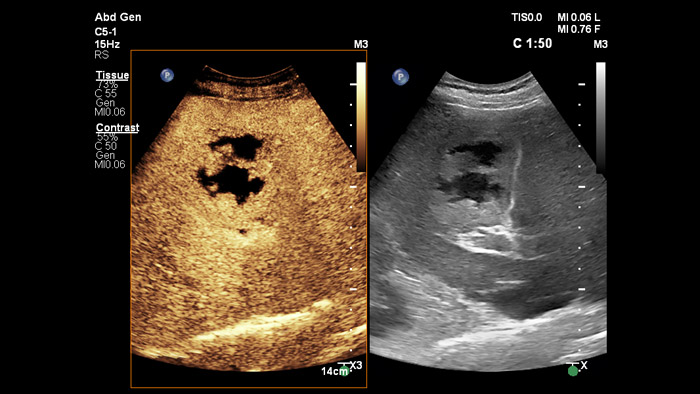

Ultrasound contrast agents can transform the role of ultrasound, allowing clinicians to study the enhancement patterns of liver lesions in real time. With Philips ultrasound, contrast enhanced ultrasound is seamlessly integrated into the standard workflow.